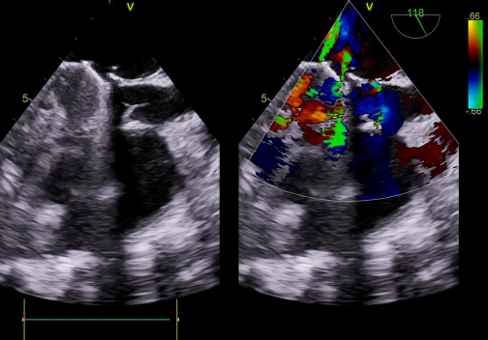

TEE, TEE and Floro showed both the leaflets to be stuck, almostno flow across the PV. The RV was higely dilated and there was severe RVdysfunction

Since TLT was not possible and surgeon refused for emergencyTranscatheter valve disruption was planned. The issues involve in the procedure were 1.Septal Puncture -due to pericardial patch in IAS, alteredanatomy due to Sx & ac dilatation of LA- Angle of puncture and Site ofpuncture. 2 Selection of wire3.Balloon- Size, make ( Compliant Vs NC), 4.Complication-like disc embolization, stuck disc leading to ac severe MA and strud fracture. The septa puncture was done as standard approach, a V18 wirewas parked in PV through a 7f Mullin sheath, Straight Turmo wire was was takenthrough a 6 JR to cross the valve and a 6 x 40 Armada balloon was dilatedacross the disc. Good acute result was obtained. The LA mean decreased from36-40 to 10-12mmHg. Post procedure the inotropic support, O2 demand decreasedover next 12 hr. However after 24 hr pt developed refractory RH failure and persistentanuria requiring SLED. And pt succumbed to the procedure 3 days after theprocedure.